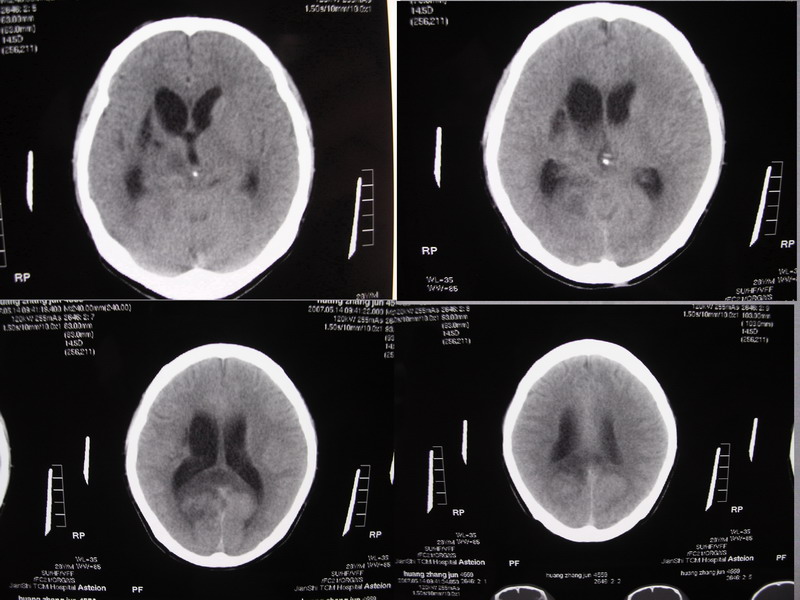

以下是引用余辉在2007-5-14 17:03:00的发言:[br]右侧脑室颞极后方可见高密度块状影,颞极呈杯口状推挤前移,右侧大脑脚及丘脑上部受推挤向对侧移位,右丘脑区结构紊乱,增强扫描病灶有不规则强化,以下部颞极后方为著。胼胝体压部及右枕叶视辐射区低密度改变,右基底节区低密度改变,双侧脑室不对称积水征象,意见:1颞极后方—右丘脑区占位性病变,如室管膜瘤等2脑血管疾病如moyamoya,局部脑血管畸形等3脑膜炎等后遗改变,建议mr及脑血管造影检查[br][br][本贴已被 余辉 于 2007-5-14 17:05:26 修改过]

以下是引用千里草在2007-5-14 15:54:00的发言:[br]考虑:1、双侧梗阻性脑积水;[br] 2、右侧基底节区缺血性脑血管疾病。

以下是引用ssmmxx在2007-5-14 18:05:00的发言:[br]颞极后方—右丘脑区占位性病变,如室管膜瘤等2脑血管疾病如moyamoya,局部脑血管畸形等

以下是引用qiuleiyu在2007-5-14 18:43:00的发言:[br]支持;1,交通性脑积水(病脑后遗征?)2,右基底节及胼骶体压部低密度灶伴轻度占位表现,结合年龄考虑moyamoya,建议dsa.[br]